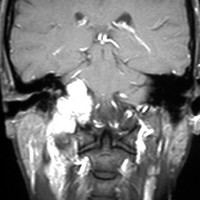

左は1991年,右は2006年のMRI画像です。15年間で腫瘍のサイズは変わっていません。

1991年に50代の女性にみつかったものでした。黄色に示したルートで摘出できないわけではありませんが,右後頭部が腫れてきたという訴えとホルネル症候,軟口蓋麻痺しかなかったので,何も治療しないでほっておきました。2016年まで25年間観察し続けました。症状の悪化は全くなく元気に暮らしておられます。グロームス腫瘍はある一定の年齢になると増大しないという性質を持っている良性腫瘍です。これを大々的な頭蓋底外科手術で摘出するするという愚を犯してはなりません。